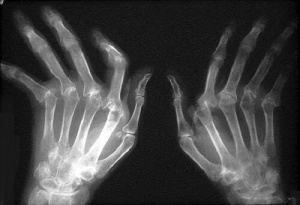

Selkein ja yleisin oire on turvotus ja tulehdus nivelissä, joka aiheuttaa kipua. Useimmiten ensioireet alkavat joko jalassa tai sormissa pikkuhiljaa. Etenkin sormien aamujäykkyys, arkuus ja kipuilu on yleistä. Muita alueita, joilla nivelreuma voi vaikuttaa ovat ranteet, olkapäät, hartiaseutu, varpaat, lantio, polvet, varpaat ja nilkat. Useimmiten nivelreuman oireet ovat symmetrisiä, eli molemmat kädet tai jalat alkavat oireilla samaan aikaan.

Kipeisiin niveliin voi kehittyä myös nivelkyhmyjä, jotka vaihtelevat kooltaan muutamasta millimetristä pariin senttiin. Etenkin sormiin ja jalkoihin syntyy kyhmyjä. Pitkälle edennyt tauti voi vääntää sormia epäluonnolliseen asentoon.